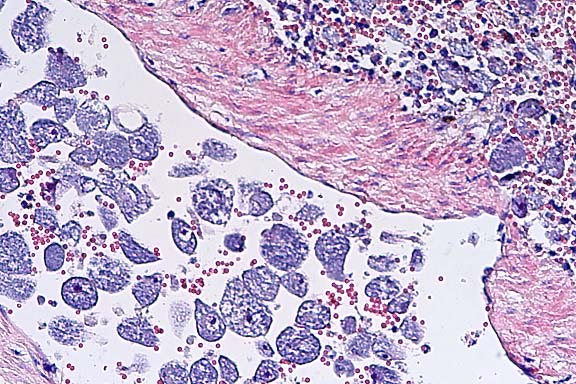

40x

obj.

- Case 3-4. Liver. Demonstrates focus of epithelioid

macrophages replacing normal hepatic cords. These cells are filled

with ill defined rod shaped structures.

- Case 3-4. Lung. Similar clusters of epithelioid macrophages

and lymphocytes expand alveolar septa near moderate sized blood

vessels. Macrophages contain granular to rod shaped material.

obj. Zeil-Neilson

- Case 3-4. Lung. Cell clusters adjacent to vessels

like those described above contain myriad acid fast bacilli.